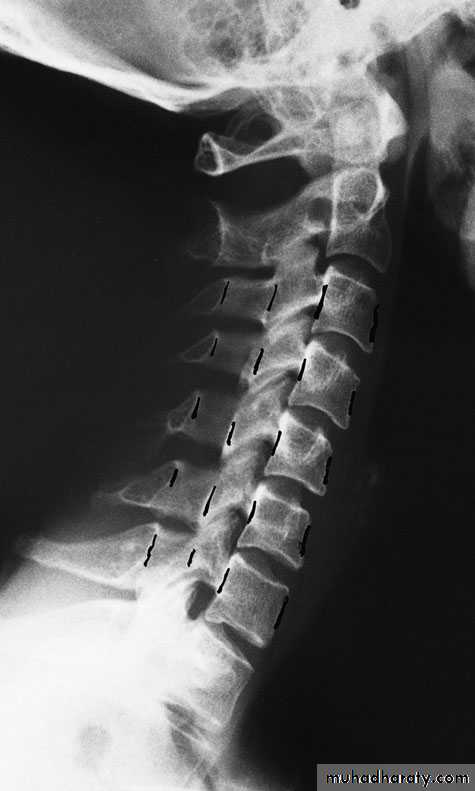

Cervical Spine X-RayLateral radiograph

A/P radiographThoracic Anatomy